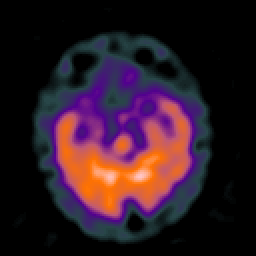

Huntington's Chorea, MR -- Slice #6

[Home][Help][Clinical] Slice 6